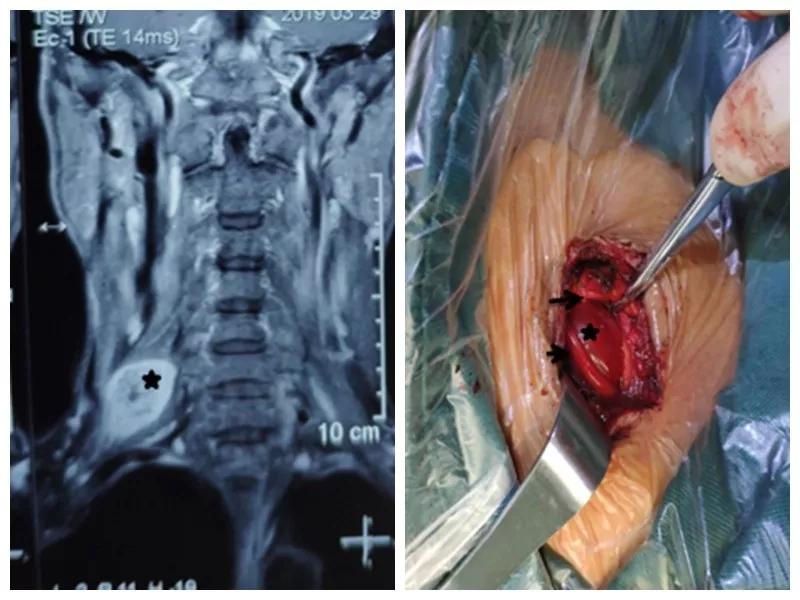

家住户县的王师傅一年前无意中发现右颈部长了一个“包”,当时并未在意,但是他发现这个“包”逐渐增大,并且伴有压痛,按压这个“包”时还可引起右胳膊疼痛,在当地医院就诊,未见好转,在我市某三甲医院检查及包块穿刺活检示右侧颈部神经鞘瘤,医生告诉他可以手术切除,但是风险很大。王师傅慕名来到按摩视频 骨一科就诊,严少荣主任接诊后立即安排住院治疗,并安排由西安市手外科常委王涛主任医师及主治医师张磊组成治疗小组。积极进行术前检查,发现右颈部肿瘤有3×3×3 cm大小活动性差的肿瘤。并有触电样感觉向肢体放射。经过制定缜密手术方案,严主任细心耐心告知患者手术的风险性,并安排术中神经电生理监测,提高手术安全性,由王涛主任医师、张磊主治医师和麻醉医师李楠及手术护士组成手术团队,在全麻下行右侧颈部神经鞘瘤切除术,术中发现此神经鞘膜瘤巨大,位于臂丛神经上干并包饶颈5.6神经,与周围组织黏连严重,由于该肿瘤起源于神经根纤维许旺氏细胞,遂着肿瘤不断生长,将神经干内正常神经纤维挤向肿瘤四周,包含在神经外膜内形成肿瘤的“包膜”呈鱼肉样。王涛主任医师在仔细保护神经的情况下采用“层层剥离挤出法”将肿瘤取除,避免了误将含正常神经纤维的“包膜”随肿瘤一起切除,造成神经干损伤及缺失,从而造成上肢功能的不可逆障碍的悲剧。术后经过主管护士解妍及全体医护人员的精心治疗护理,王师傅原有神经压迫症状消失,无任何感觉运动异常,术后再次病检符合神经鞘瘤。王师傅满意出院。

通过此例罕见臂丛神经上干神经鞘瘤病人治疗,标志着我科在高位臂丛神经干手术达到一个新高度。